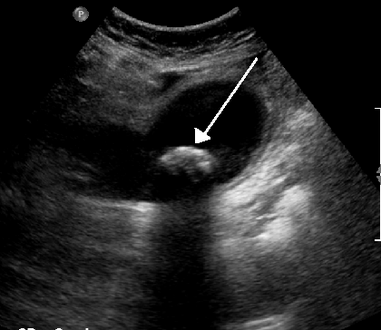

في الموجات فوق الصوتية على البطن، عادةً ما يكون لحصوات المرارة الغارقة ظل صوتي خلفي. في حصوات المرارة العائمة، يُشاهد صدى الصدى (أو قطعة أثرية على شكل ذيل المذنب) بدلاً من ذلك في حالة سريرية تسمى الورم العضلي الغدي تكون هناك علامة أخرى هي ثالوث جدار الصدى والظل (WES) (أو الظل المزدوج القوس) والذي يعد أيضًا من سمات حصوات المرارة.[37]

حصوة حجمها 1.9 سم في عنق المرارة وتؤدي إلى التهاب المرارة كما يظهر في الموجات فوق الصوتية. هناك سماكة في جدار المرارة بمقدار 4 ملم.